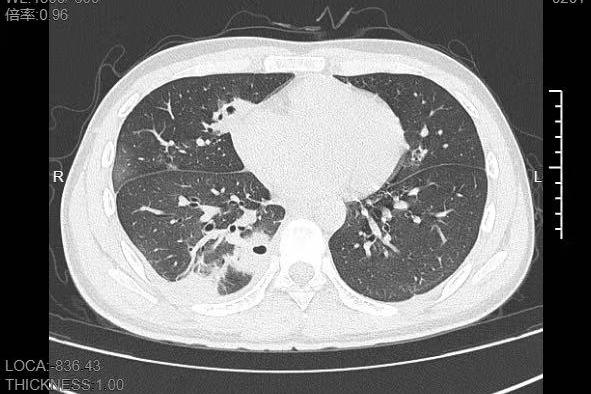

熬到第三天,小林已經燒到39℃,趕緊來到寧波大學附屬第一醫院就診。接診的呼吸與危重症醫學科丁群力主任醫師一看他的癥狀,立刻安排了CT檢查。結果顯示:小林的肺里有十幾個空洞,部分肺組織已經壞死,這是典型的血源性肺膿腫

小林的CT影像顯示肺里有多個空洞